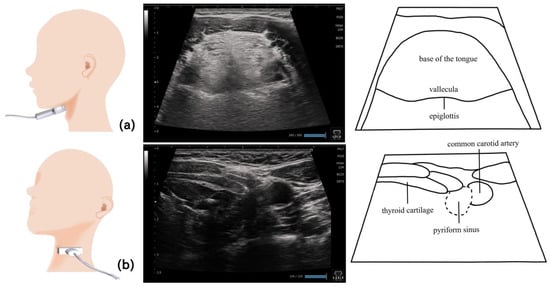

11. Pharynx (Figure 10 and Figure 11)